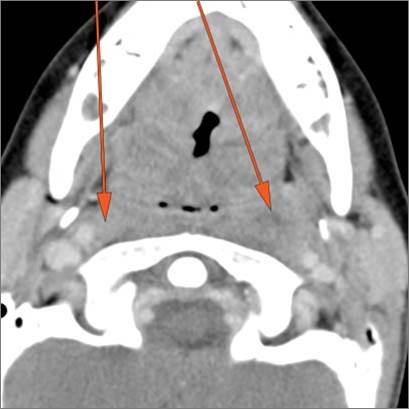

There is suppurative retropharyngeal lymphadenopathy. [Yes/No]

If there is suppurative retropharyngeal adenopathy what is the maximum short axis dimension of the largest suppurative node. Measurement [Yes/No]